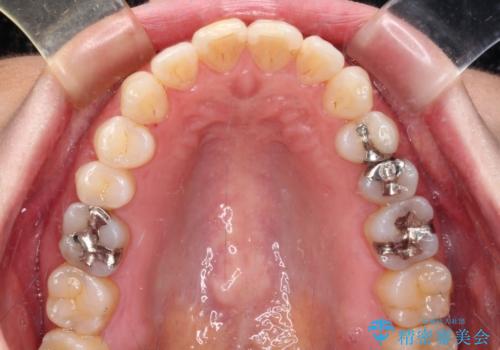

- 銀歯をセラミックにしたいとのことで来院された患者様です。

まず麻酔をして銀歯を外し、むし歯を除去し、形を整えて型取りします。

そして次の来院時、セラミックインレーを装着し、噛み合わせなどの調整を行います。

それを左右に分けて行いました。